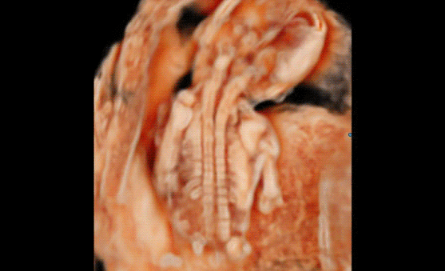

3D/4D成像方面,Hera i 10通過結合先進的圖像渲染技術,著重加強了邊緣和小結構的可視化能力。